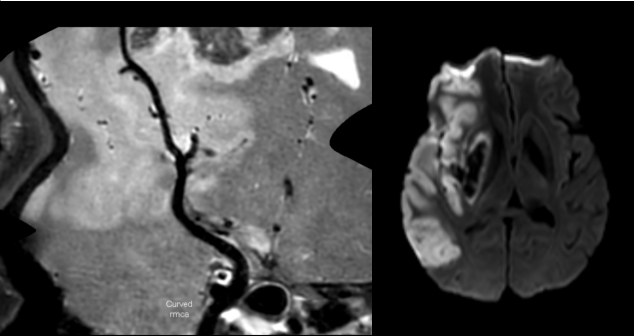

4招丨发现血管炎性病变

c942acd936317f3ed8349105fac4e327.png

左图T1W平扫见大脑中动脉M2段管壁增厚明显并呈等高信号,右图T1W增强后见管壁强化明显,提示该处有活动性炎症。

91afb25b92d13a6bf5254e21724c0d78.png

3D曲面重建后更直观明确血管壁炎症的位置和情况。